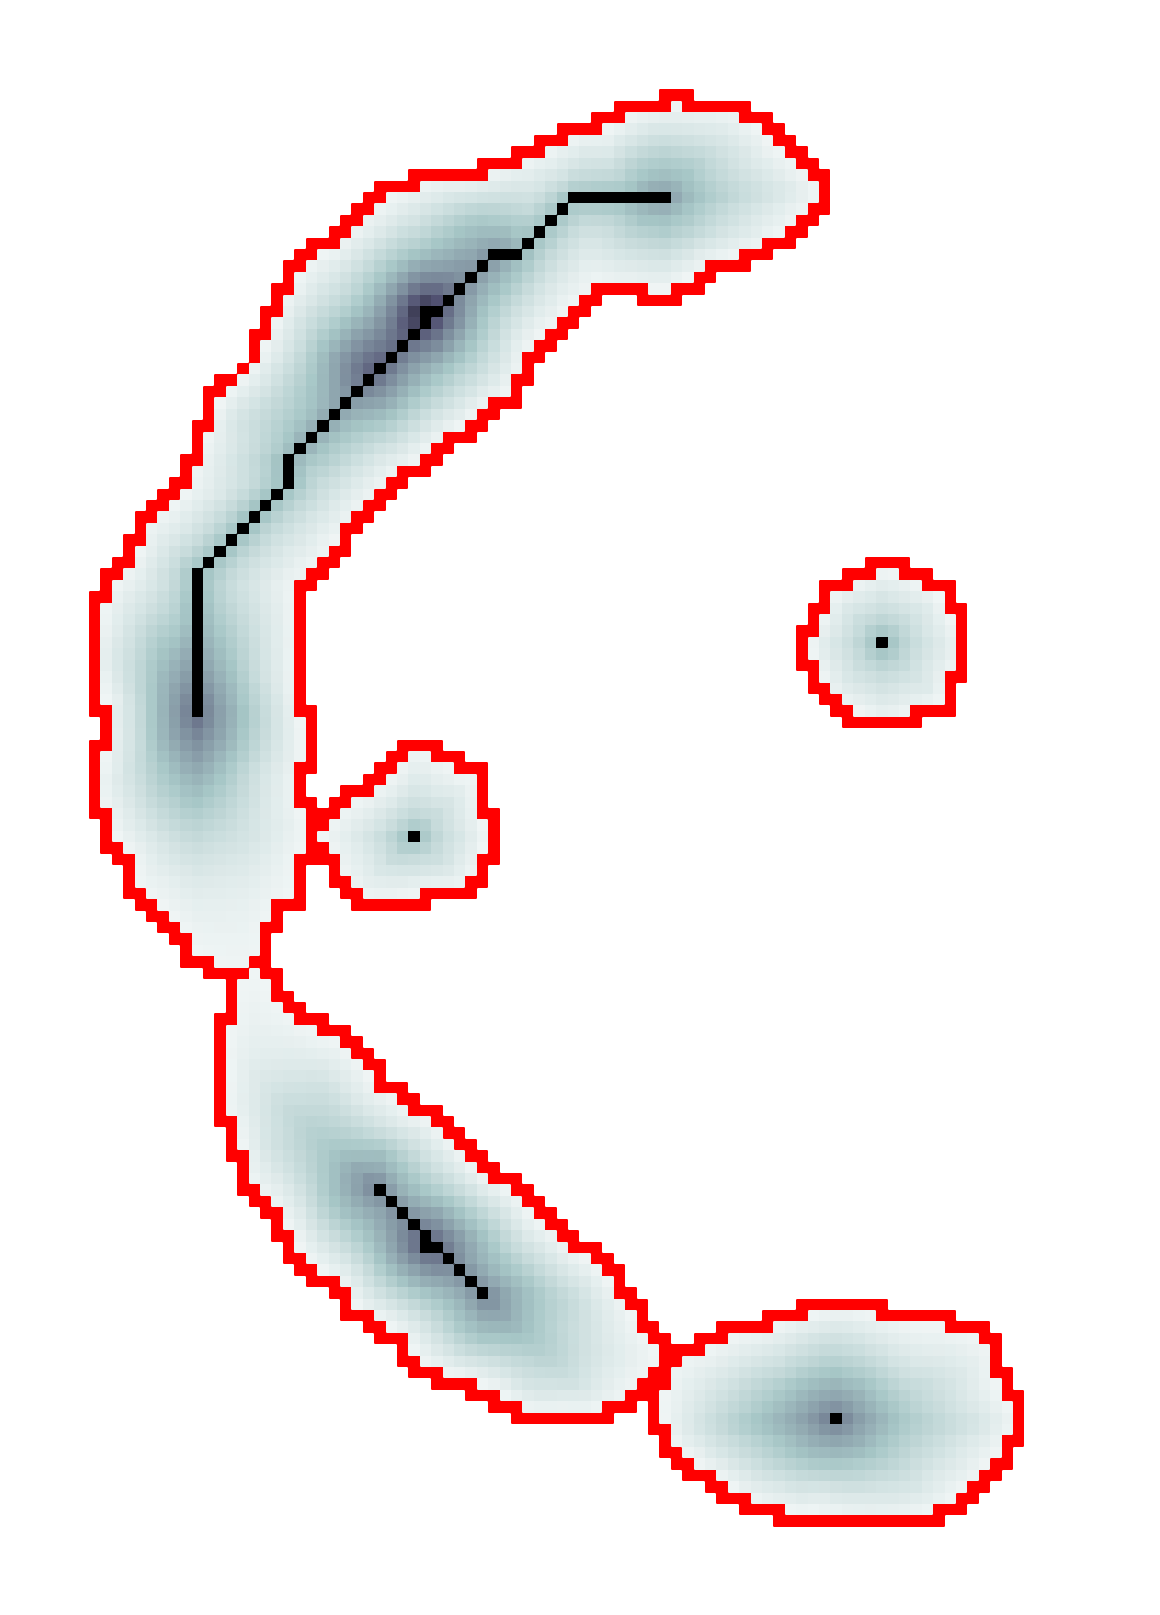

The scalar vesselness responses of both HCP and PC images are determined using the state-of-the-art Frangi filter (FFR) [8], and Optimally Oriented Flux (OOF) [12]. Also, the connected vesselness map (CVM) and the associated tensor field (TF) are synthesized for the same dataset using VTrails. The connectedness of the considered scalar maps is qualitatively assessed and the TF is inspected as proof of concept in section 3.1.

3.1 Connectedness of the Vesselness Map

Fig. 3 shows the connectedness of vessels recovered from state-of-the-art vascular enhancers and curvilinear ridge detectors FFR and OOF together with the proposed CVM for the synthetic HCP and the real PC images.

On the synthetic phantom, FFR shows a fragmented and rough vesselness response in correspondence of irregularly shaped sections of the structure. Also, the response at the bifurcation is not smoothly connected with the branches (triangular loop). Conversely, OOF recovers the phantom connectedness at the branch-point, and the vesselness response is consistent along the tortuous curvilinear section, however ghosting artifacts are observed as the shape of the phantom becomes irregular (C-like) or differs from a cylindrical tube. Also, close convoluted structures, which change scale rapidly in the HCP, produce inconsistent responses of OOF (fig. 3). CVM shows here a strongly connected vesselness response in correspondence of both regular and irregular tubular sections, with local maxima at structures’ mid-line. The connectedness of the structures is emphasized regardless the complexity of the shape, and it resolves spatially the tortuous curvilinear ‘kissing vessels’ without additional ghosting artifacts, despite the smooth profile.

Similar results are observed on the PC dataset: FFR has a poor connected response in the noisy and low-resolution image. Vessels are overall enhanced, however thin and fragmented structures remain disconnected. Overall, the vesselness response is not uniform within the noisy structures, where maximal values are often off-centred. A more consistent response is obtained from OOF, where the connectedness of vessels is improved. Maximal response is observed at the mid-line of vessels, however, noise rejection is poor. CVM strongly enhances here the vessel connectivity. The fragmented vessels of PC have a continuous and smooth response in CVM with higher values and a more defined profile. Large vessels shows solid connected regions with local maxima at mid-line as in OOF. Conversely from OOF, CVM shows improved noise rejection in the background.

The respective tensor fields (TF) synthesized on both HCP and PC show consistent features. The TF’s characteristics are in line with the connectedness of CVM: enhanced and connected vessels are associated with high anisotropy, whereas background areas show a predominant isotropic component.